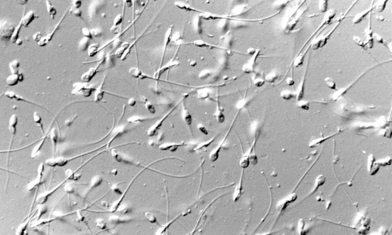

At Institut Marquès, we have one of the most advanced embryology laboratories in Europe. Equipped with state-of-the-art technology and led by a team of internationally renowned embryologists, our laboratory is the heart of the clinic and our treatments.

Systems such as Embryoscope, Time-Lapse, and cutting-edge embryo culture techniques guarantee the utmost care and control in the development of each embryo. State-of-the-art technology to increase your chances of pregnancy.